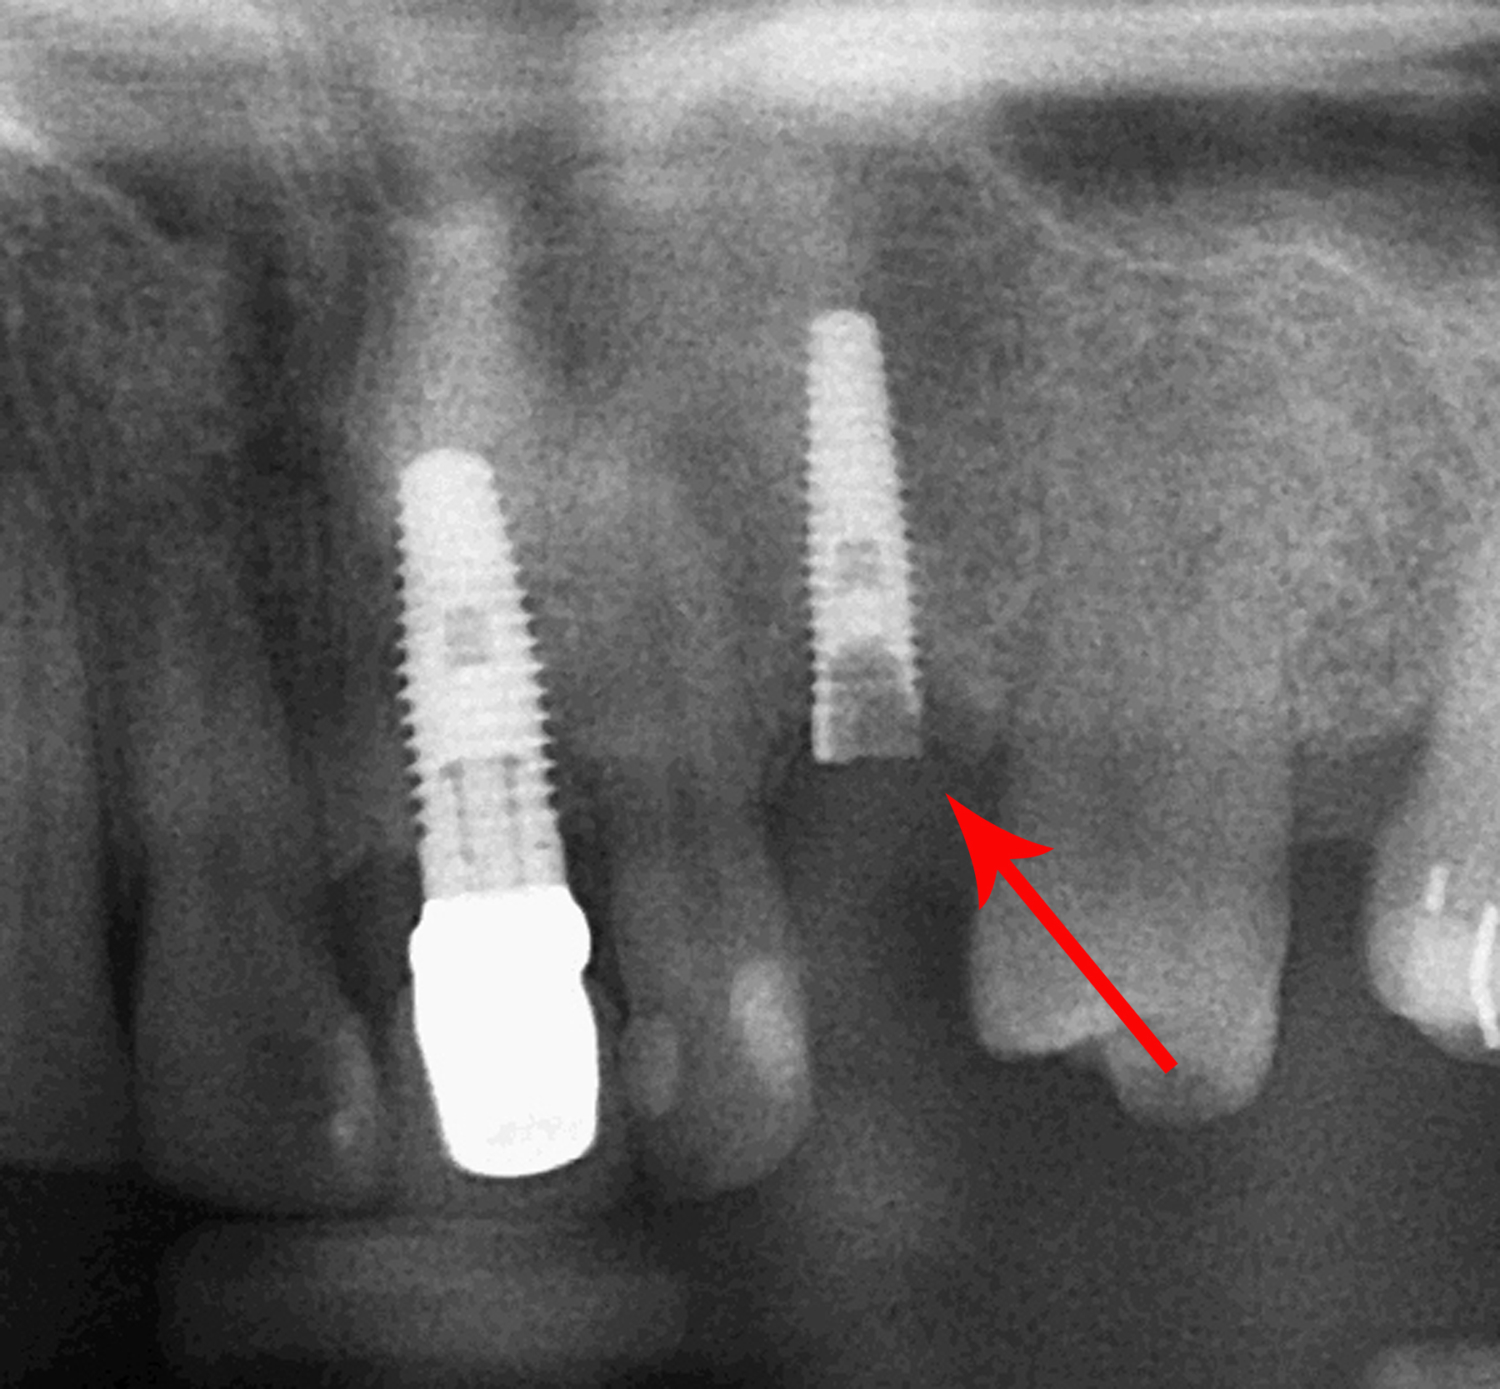

Troubleshooting Failed Dental Implants Causes and Solutions NY Implant Clinic How To Tell If Your Dental Implant Has Failed Treating a failed dental implant always involves extracting the implant, or else it can become infected. Early signs of dental implant failure often include severe pain, discomfort, swelling or inflammation of the gums, and the implant. Implants are comprised of a crown (the false tooth) affixed to a post that’s embedded into your jaw. Learn how to spot failed implant. How To Tell If Your Dental Implant Has Failed.